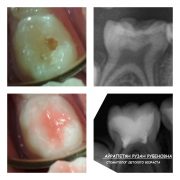

ведущий специалист по восстановлению молочных зубов коронками и лечению под наркозом.

2017г. — Обучение «Лечение осложнений кариеса у детей и подростков»

2017г. — Обучение «Дентальная травматология в детской стоматологии или травмы временных зубов. Восстановление временных зубов коронками»